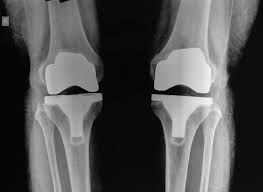

The company ORTHOPEDIC NIKIFOROV was founded in 1998 by the candidate of medical sciences. doctor of orthopedic-traumatologist of the highest category Nikiforov IA Owing to high professionalism and results of work, ORTONIC has gained well-deserved reputation and reputation among colleagues and population of Dnepropetrovsk region and CIS countries (Russia, Moldova, Armenia, etc.). The principle of the enterprise is NO IMPOSSIBLE, it is based on knowledge, experience and active implementation of modern technologies in orthopedics and traumatology. Conservative methods of treatment include individual selection of medicines, therapeutic blockades, manual therapy, massage, physiotherapy (vibration table, magnetotherapy, bioptron, electromyostimulation, etc.), rehabilitation with the suggestion of the necessary concomitant devices and means for the fastest recovery (corsets, bandages, various joint fixators, crutches, walking sticks, etc.). Various minor invasive interventions (chymonucleolysis, vertebroplasty, kyphoplasty, percutaneous nucleoplasty using cold plasma) that are performed on an outpatient basis are successfully used to treat problems associated with spine pathology. The latest modern treatment methods introduced in our company are endoscopic operations using the TYSSES technique of Joimax (Germany) with intervertebral hernias, stenosis and other pathologies of the spine, which allow to avoid complications occurring during open operations and the accompanying general anesthesia. We have many years of successful experience in traditional and modern minimally invasive endoprosthetics of large and small joints, which remains the main direction of our activity. Our company is the exclusive representative of the German company IO International Orthopaedics Holding GmbH, which based on the already known prostheses, its ideas and technological capabilities, has developed and implemented a new concept in hip replacement - an artificial joint prosthesis (ICON). We assist interested colleagues in training the operative technique for installing an artificial joint prosthesis - ICON, both in the workplace and in Germany. For 20 years we have been successfully cooperating with Sanitatshaus Gerd Klinz ortho team, an enterprise that for 20 years has been one of the leading places in Germany for the production of functional prostheses of the upper and lower limbs, as well as cosmetic prostheses of limbs and other body parts (nose, ears, eyeballs, fingers). We have an atmosphere of friendliness and human participation. Politeness, benevolence, the desire to understand and help is the basis of our attitude towards patients. We are always glad to see you and will do our best to make you feel great! We are waiting for you at: Ukraine, Dnepr, Gagarin Ave., 13 (under reconstruction) on all questions to address: tel .: +38 (050) 488-88-92 E-mail: orthonik.ukr@gmail.com Germany, Spine Nano Klinik, Zeppelinstr. 21, Potsdam Tel. +4901801121919 E-mail: kmw.nikiforov@hotmail.de